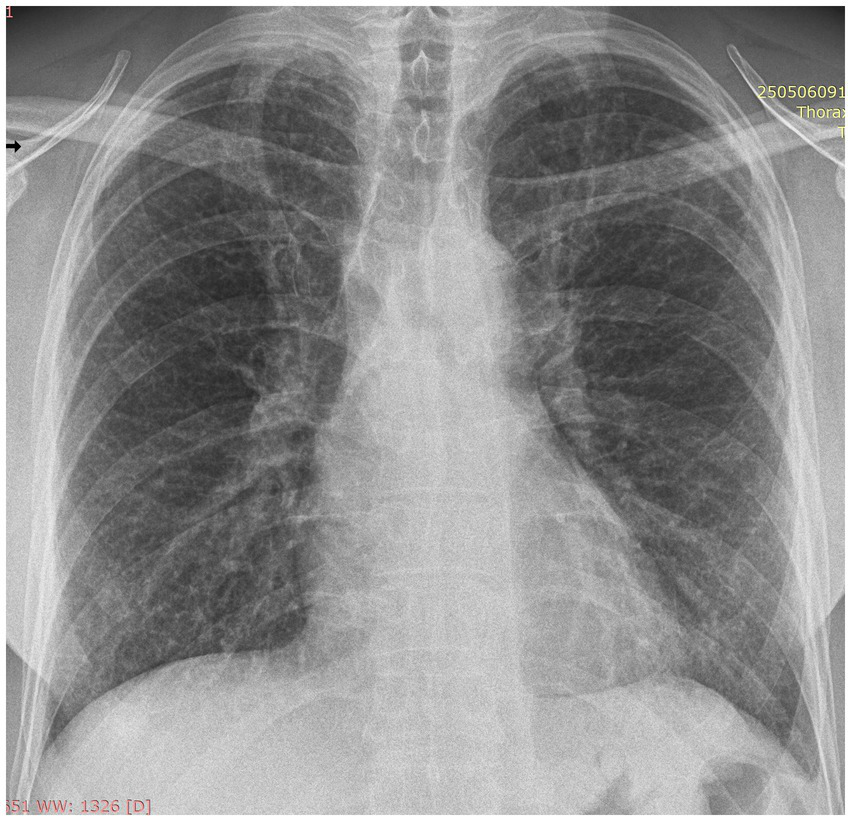

To best illustrate the complexity of the sarcoidosis–tuberculosis diagnostic spectrum, we present the case of a 48-year-old Caucasian male individual admitted with constitutional symptoms, including significant weight loss (10 kg), non-productive cough, and mild exertional dyspnea, with an insidious onset approximately 3 months prior to admission. The patient had no significant professional exposure (he was a taxi driver) and had no recollection of any previous contact with TB patients in his family and professional environment. He had no family history of sarcoidosis, other granulomatosis, or TB. Clinical examination at presentation showed no abnormal lung sounds. No other abnormalities were found, including absence of fever, peripheral lymph node enlargement, or findings related to the eye, heart, or abdomen. Chest X-ray showed multiple micronodules distributed especially in the upper regions of the lungs (Figure 1). High-resolution chest computed tomography (CT) confirmed multiple bilateral pulmonary nodules, predominantly in the upper lobes, exhibiting a perilymphatic distribution. These findings were associated with mediastinal lymphadenopathy and minimal bilateral pleural effusion (Figures 2, 3).

Figure 1

Postero-anterior chest X-ray at presentation: multiple ill-defined, low-intensity micronodules distributed bilateral, with upper lobe predominance.